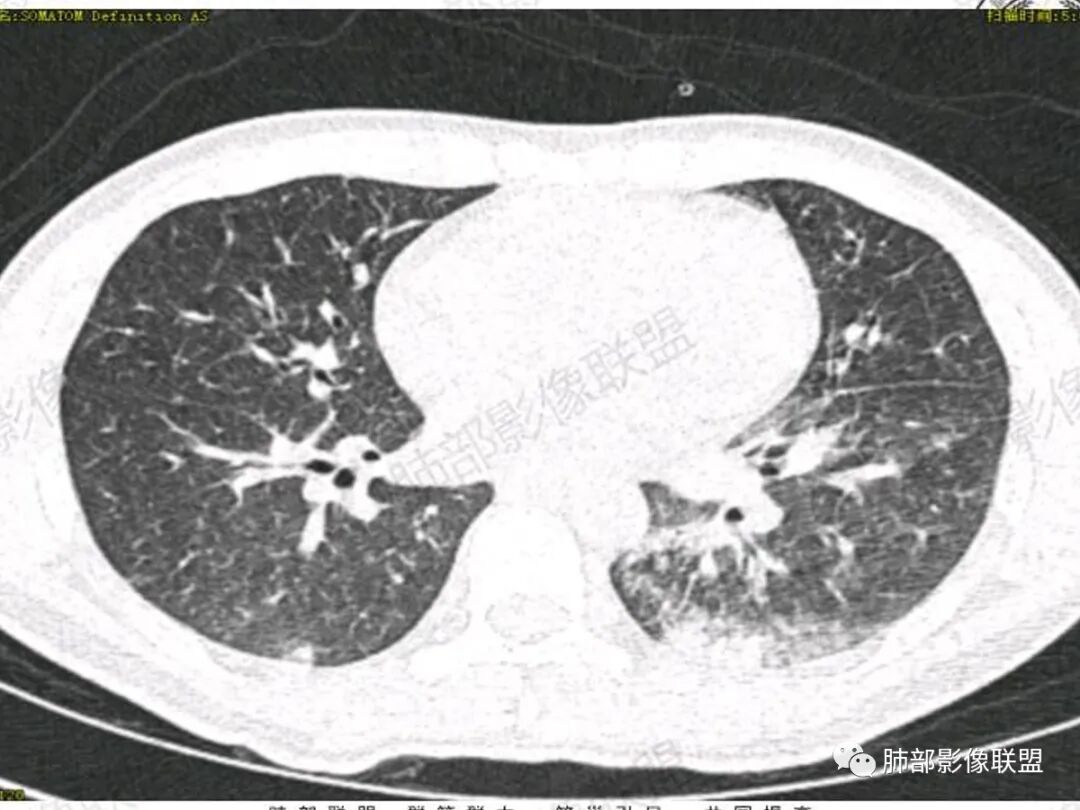

双肺上叶,下叶背段多发斑片状实变影,以胸膜下分布为主,部分重力作用,以背侧为主,部分小叶间质增厚,部分周围伴有散在磨玻璃影,边界欠清,临床急性病程,血象增及PCT明显增高,意识模糊,考虑:吸入性肺炎?鉴别:AHP?CEP?PCP

双肺叶透亮度对称性减低,呈磨砂状,小叶间隔规则增厚,上叶为甚,左右肺叶中轴间质增厚(示淋巴回流障碍),双肺叶弥散磨GGO征,以肺腺泡分布,双肺上,下叶融合片状,有重力分布特点,心脏大,肺动脉干增粗,首选心源性肺水肿,但无胸腔积液。与急性肺损伤和ARDS鉴别

影像学提示肺水肿与肺泡腔液性渗出(小叶间隔增厚+实变+重力趋势),上叶显著。

双肺弥漫性病变以上肺,向心性,背部分布为主,肺动脉干无增粗,急性起病,典型的吸入性肺炎。

既有重力分布特点,也有吸入性特点,这个病例缺乏了特殊病史,是喝醉后还是别的原因引起的误吸。

青年男性,气促7小时入院,意识模糊,白细胞及中性粒明显增高,PCT增高,CRP不高,心率快,体温正常,血压正常。胸部CT:双肺上叶小叶间隔光滑增厚,中轴间质增厚,弥漫性磨玻璃、多发斑片影,以上肺、背侧分布为主。影像表现考虑为肺水肿。病因:病史不支持肾功能衰竭、心源性、高原性肺水肿,无发热,似乎也不支持细菌、病毒、真菌等感染引起。吸入毒物?吸入水?

病灶的分布以上肺为主

结合病史,最终诊断是 “急性烟雾吸入性肺损伤”,影像学表现主要是肺水肿及弥漫性肺泡损伤改变,因为烟雾气体吸入肺内分布以上肺显著,因此影像学表现也是累及上肺更明显。损伤因素包括大量一氧化碳 二氧化碳 一氧化氮等燃烧产生的有毒气体,也有烟雾粉尘颗粒对气道黏膜的损伤。